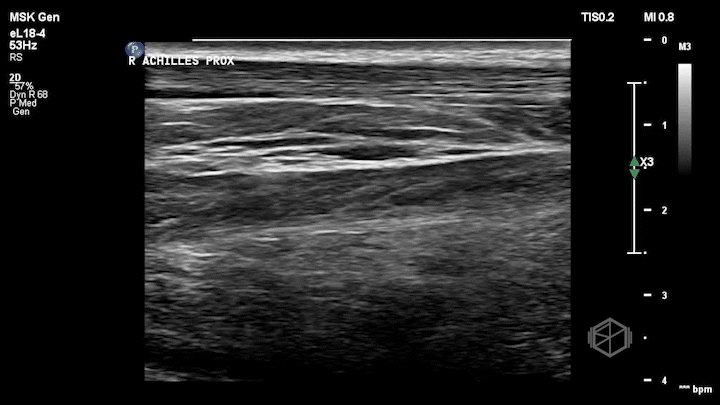

Dr. Simon grabbed the ultrasound and performed this POCUS:

Notice how the right (non-affected) Achilles tendon is nice and smooth. It is the first structure from top to bottom and appears as a thin fibrillar structure.

The left (affected tendon) is irregular with a quite obvious visible tear with some surrounding edema (anechoic fluid).

Dr. Simon included the unaffected tendon for comparison which is a great thing to do when performing with extremity ultrasounds.